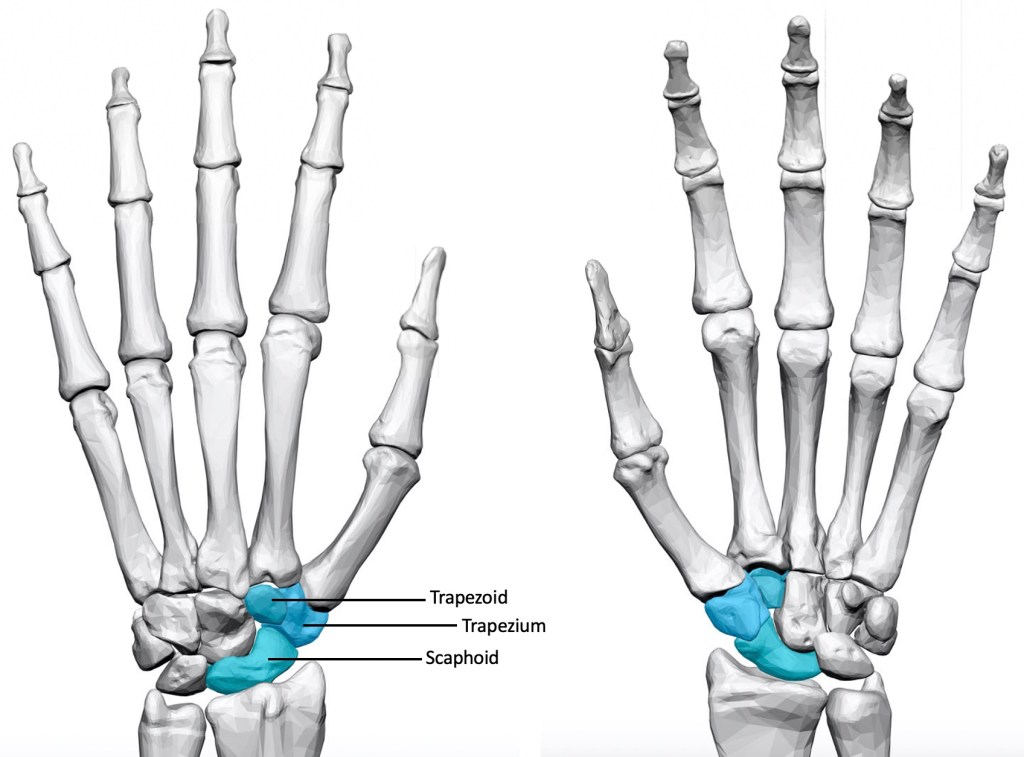

The triscaphoid joint (also known as the STT joint) is located within the wrist joint, and involves the Scaphoid, Trapezium and Trapezoid bones. This joint is important because it provides a strong and stable link between the two rows of bones in the wrist, and transmits force from the thumb across the wrist joint. Arthritis in this joint is relatively uncommon compared to arthritis at the base of the thumb, but affects around 8% of women over the age of 50. The majority of patients with triscaphoid osteoarthritis also have base of thumb arthritis.